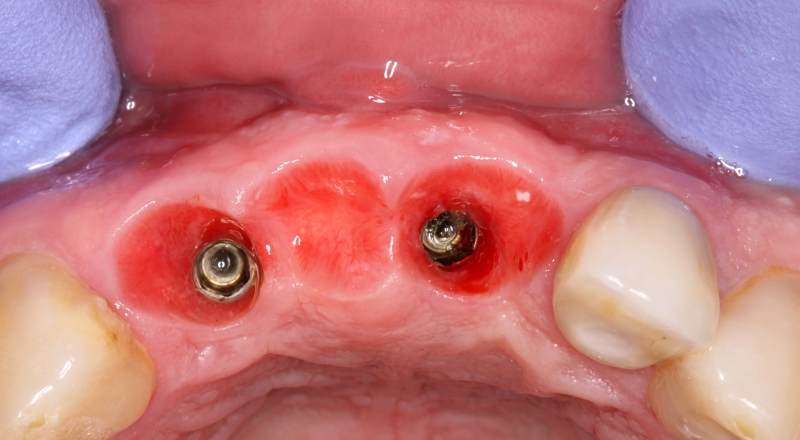

GBR and soft tissue augmentation with cerabone® and mucoderm® - H. Maghaireh & V. Ivancheva

Initial situation: missing teeth #11 & 12 and badly broken #21 root